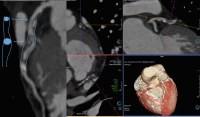

Abbildung 5: Nach dem Risiko-Score Niedrigrisikopatient (40 Jahre, Grenzwerthypertonus, LDL-Cholesterin 120 mg/dl), in der CCTA: hohe Plaquelast im LAD-Bereich mit positivem Remodelling. Dieser Patient profitiert sicher von einer Hochdosis-Statintherapie und wahrscheinlich von einem Thrombozyten-Aggregationshemmer. LAD: Left Anterior Descending Artery